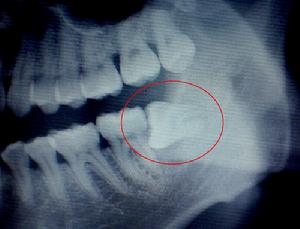

6、侵犯鄰牙:通常患者不自知,而由牙醫以X光診斷得知。智齒由於萌發的空間不足,而會倒在第二大臼齒上,因而造成第二大臼齒清潔不易,甚至出現牙齒部分吸收的現象,造成患者不舒適或牙疼 。

4、智齒是第三大臼齒,對相鄰的第二磨牙有重要影響。由於大多數智齒是前傾阻生的,約呈45度角頂在第二磨牙上,從而形成一個牙冠夾角,容易嵌塞食物,久之導致第二磨牙齲壞,甚至牙髓炎,就算沒有那么嚴重也會影響第二磨牙的壽命。